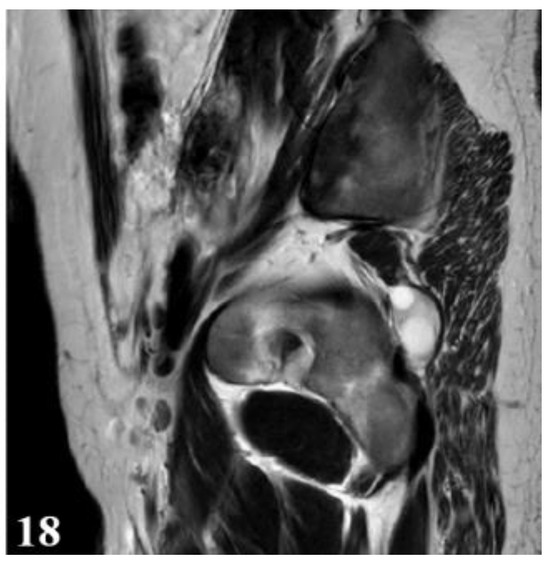

Figure 18.

T2W sequence, sagittal—Postoperative residual hydatid cyst located at the level of the left iliopsoas muscle and deep to the left gluteus maximus muscle (part 2).

Considering the impossibility of performing an ideal cystectomy, it was decided to perform an efficient drainage by closing the remaining retroperitoneal cavity after mounting a drain tube (through which the lavage and drainage slope at the base of the left thigh with tubes passed through the muscle gap is carried out). Adjacent peritoneal drainage and anatomical parietorrhaphy. Native MRI examination and post-operative intravenous post-contrast (Figure 17 and Figure 18), reveals: diffuse infiltrative-edematous appearance at the level of the iliopsoas muscle on the left side, with the presence of a collection with peripheral type gadophilia, difficult to appreciate under dimensional ratio, with a tendency to diffuse extension, developed predominantly intramuscularly at the level of the psoas muscle on the left side, with the predominant interest of its peripheral portion between 7–3 o’clock (being tangent to the external iliac vessels on the left side, with present, homogeneous flow at their level), extended to at the level of the ipsilateral iliac muscle and later in a caudal direction at the level of the iliopsoas muscle on the left side up to the vicinity of its distal insertion, after which it insinuates between the muscles of the antero-internal region of the thigh on the left side up to the border between the proximal third and the middle third of the thigh, and coming into contact on several sections with the femoral vessels on the left side, but without causing changes in caliber or flow at their level. At the level of the proximal portion there is a fistulous tract with a maximum thickness of approximately 0.7 cm, externalized at the level of the root of the left thigh in the antero-internal region which seems to communicate in depth with the previously described collection. In the proximal portion of the thigh on the left side, diffuse infiltrative-edematous changes adjacent to the previously described collection are evident at the level of the intermuscular space in the anterior region of the thigh, without being accompanied by similar changes at the level of the muscles in the anterior region of the thigh (Figure 17 and Figure 18).